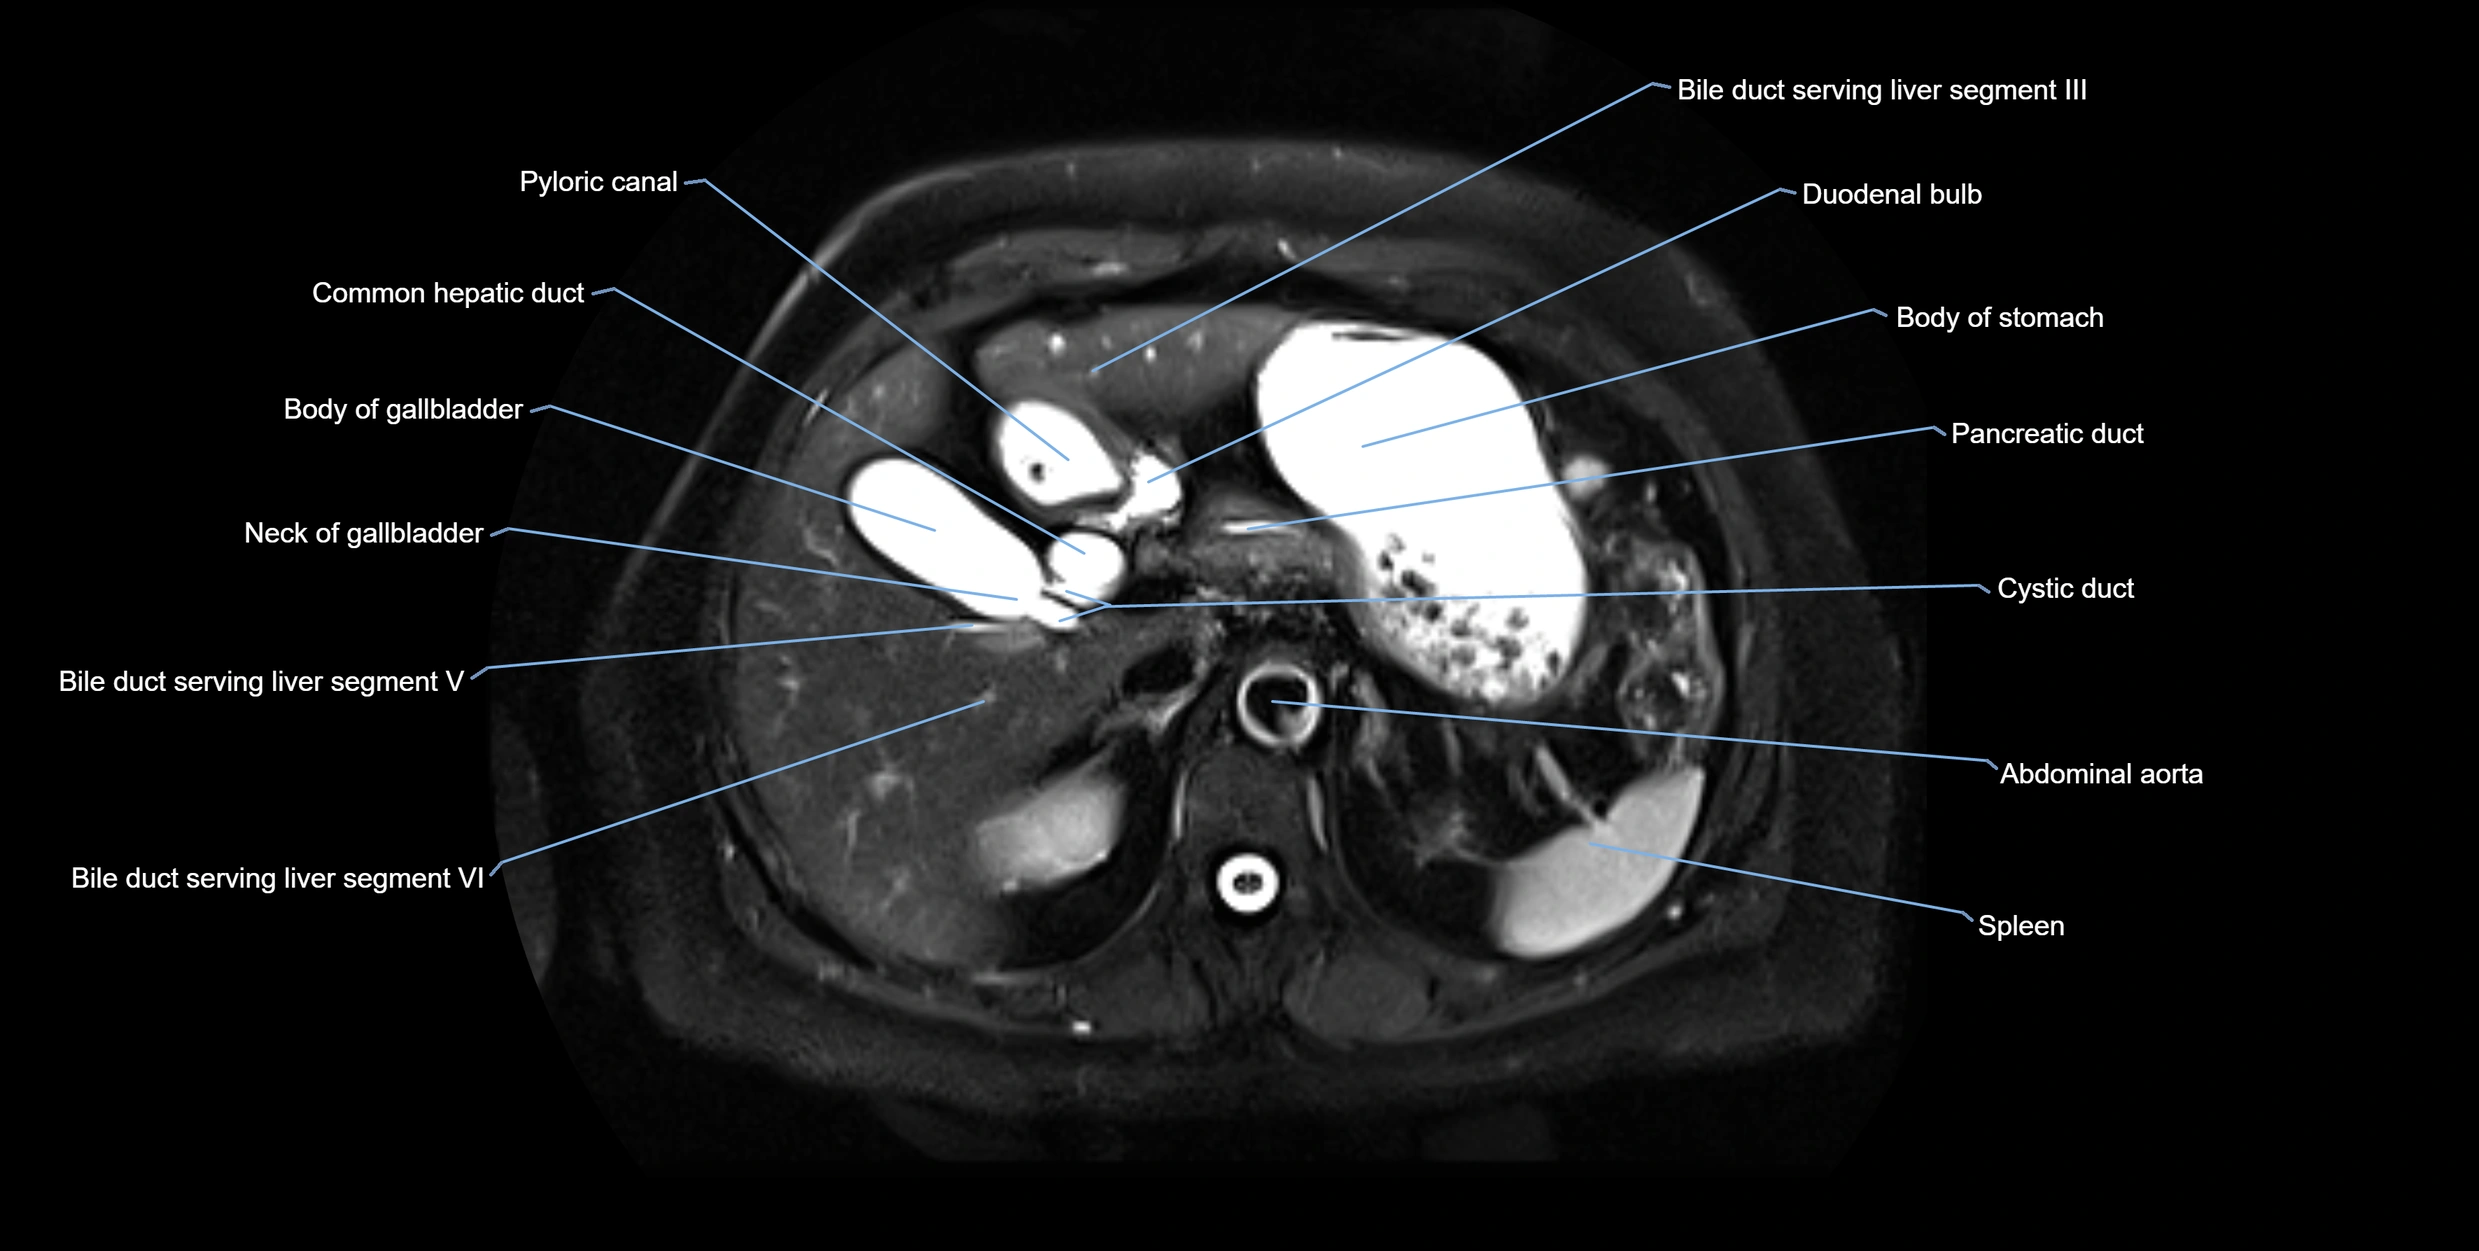

MRI image

image